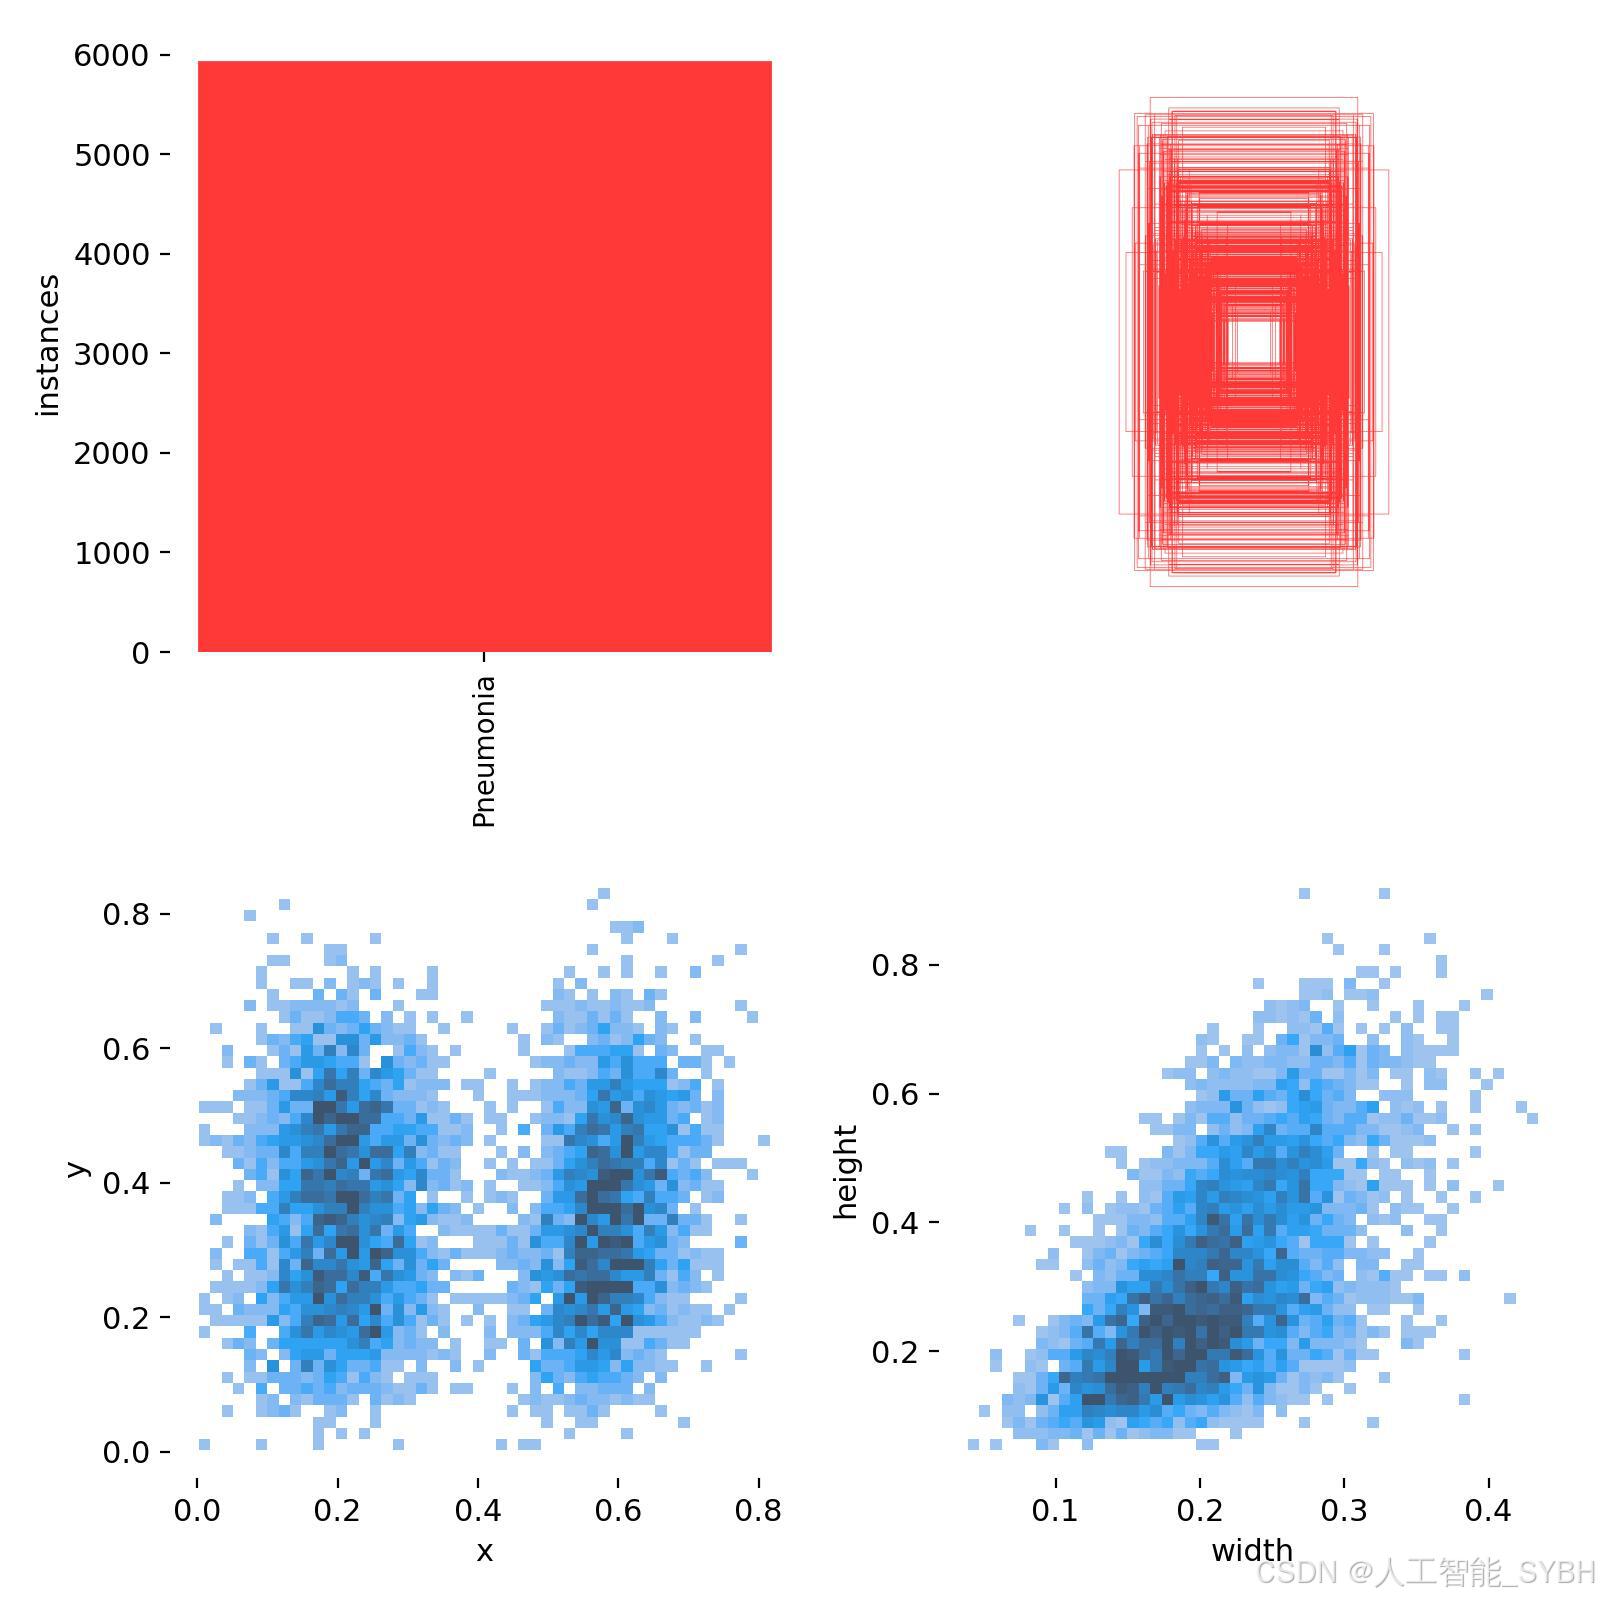

三、数据集介绍

数据集名称: 肺炎检测数据集

数据集内容:

类别数量 (nc): 1类

类别名称: ['Pneumonia']

Pneumonia: 肺炎

数据集规模:

训练集: 3772张图像

验证集: 539张图像

测试集: 1078张图像

数据来源:

数据集通过收集医院中的胸部X光片构建,涵盖了不同年龄段、性别和病情的患者,以确保模型的泛化能力。

数据标注:

每张图像中的肺炎区域均使用边界框(Bounding Box)标注,并标注对应的类别。

标注格式为YOLO格式(class_id, x_center, y_center, width, height),便于直接用于YOLOv8模型的训练。

数据集特点:

多样性: 数据集包含不同患者的胸部X光片,覆盖了多种病情和拍摄条件。

高质量: 图像分辨率高,标注精确,适合深度学习模型的训练。

平衡性: 数据集经过合理划分,确保模型在训练过程中能够充分学习特征,并在验证集和测试集上表现出良好的泛化能力。